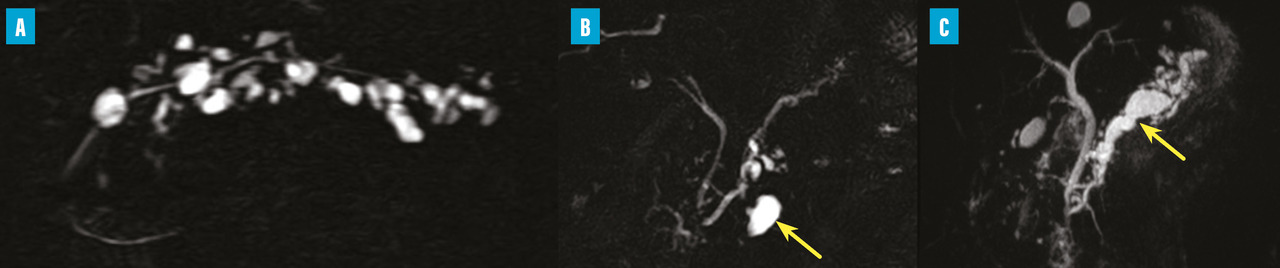

Les TIPMP sont des lésions canalaires intra-épithéliales développées aux dépens des canaux pancréatiques (principal ou/et secondaires) [fig. 1]. Elles prédominent au niveau de la tête et du crochet, mais peuvent concerner toute la glande. La composante kystique des TIPMP présente un épithélium de type mucineux avec production de mucus. Au cours du processus d’oncogenèse, des papilles commencent à se former, et différents phénotypes cellulaires distincts ont été décrits, corrélés à leur pronostic.

Toujours parmi les LKP rares à potentiel malin, on compte les tumeurs neuro-endocrines (TNE) kystiques (20 % des TNE pancréatiques) [fig. 5]. De découverte fortuite et non fonctionnelles, les TNE kystiques sont uniques, uniloculaires, bien différenciées, de bas grade, c’est-à-dire avec un indicateur de prolifération Ki67 < 3 %, et la présence d’une masse hypervasculaire (nodule) au niveau de la paroi. La partie charnue tissulaire peut être de petite taille.